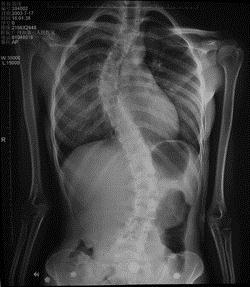

问题 病历摘要: 患者××,女,17岁,发现剃刀背畸形3个月。查体:脊柱胸段向右侧凸,腰段向左侧凸,右胸廓呈剃刀背畸形,双下肢未见明显异常。 该患者的诊断是: 提示:患者 X线片见图:

选项 A、外伤性侧弯 B、神经肌肉性侧弯 C、神经纤维瘤病 D、麻痹性脊柱侧弯 E、先天性脊柱侧弯 F、特发性脊柱侧弯

答案 F